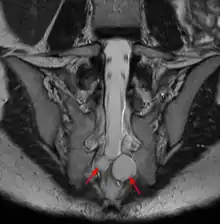

| MRI image showing a Tarlov cyst | |

MRI, or Magnetic Resonance Imaging, is considered the imaging study of choice in identifying Tarlov cysts. MRI provides better resolution of tissue density, absence of bone interference, multiplanar capabilities, and is noninvasive. Plain films may show bony erosion of the spinal canal or of the sacral foramina. On MRI pictures, the signal is the same as the CSF one.